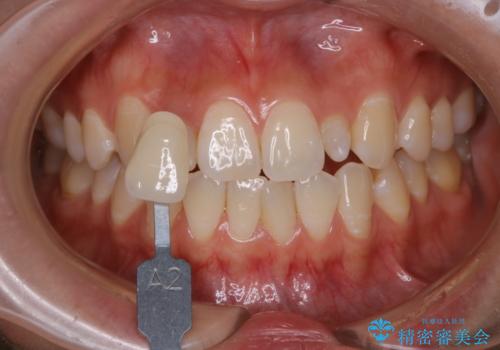

前歯のセラミックを作る前にホワイトニング

- 前歯のセラミッククラウンの型取りの前に、ホワイトニングで全体を白くしたいとのことでした。オフィスホワイトニングのエクセレントコース・トリートメントを行いました。

- 33,000円(税込)費用は治療当時の料金となります